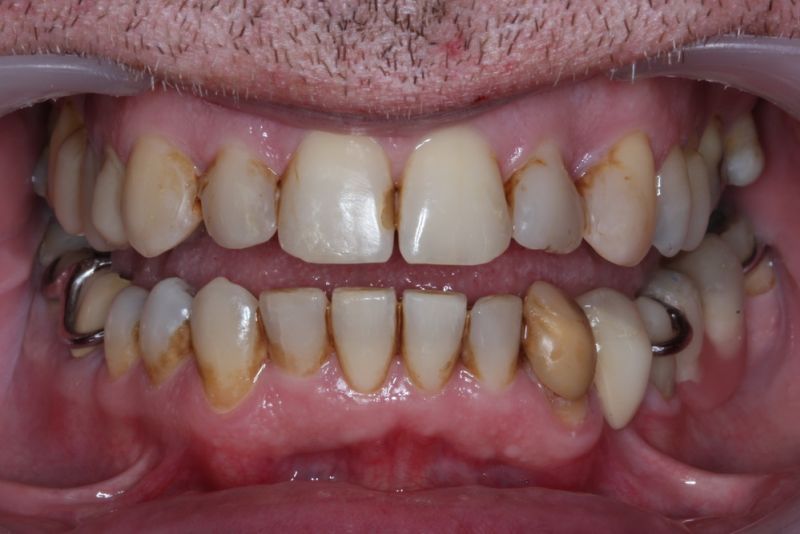

Erkennbar ist die massive Abweichung der habituellen Bisslage von der neuromuskulär zentrierten Bisslage.